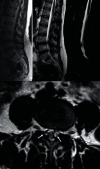

Introduction: Spinal synovial cysts (SSCs) constitute an uncommon degenerative lesion of the spine. They are usually asymptomatic but they may also cause symptoms of variable severity. SSCs are benign growths adjoining the facet joints that may induce low back pain, lumbar radiculopathy, and neurological deficit. There are different treatment options that range from conservative management to interventions like image-guided epidural steroid injection or direct cyst puncture and finally to open or endoscopic spinal canal decompression and spinal bone fusion with/without instrumentation. A discussion of current management options for this unusual disease is presented. Material and Methods. A 52-year-old female patient presented with low back pain and left leg pain. Plain radiography demonstrated instability at the L4-L5 level. Magnetic resonance images (MRIs) revealed a bilateral cystic lesion at the L4-L5 level with associated instability and degenerative disc disease at the level L5-S1. Initially, conservative treatment was performed by aspiration of the left cyst and infiltration with corticosteroids with improvement of the pain for 1 year. After this period, the radicular and the low back pain reoccurred.